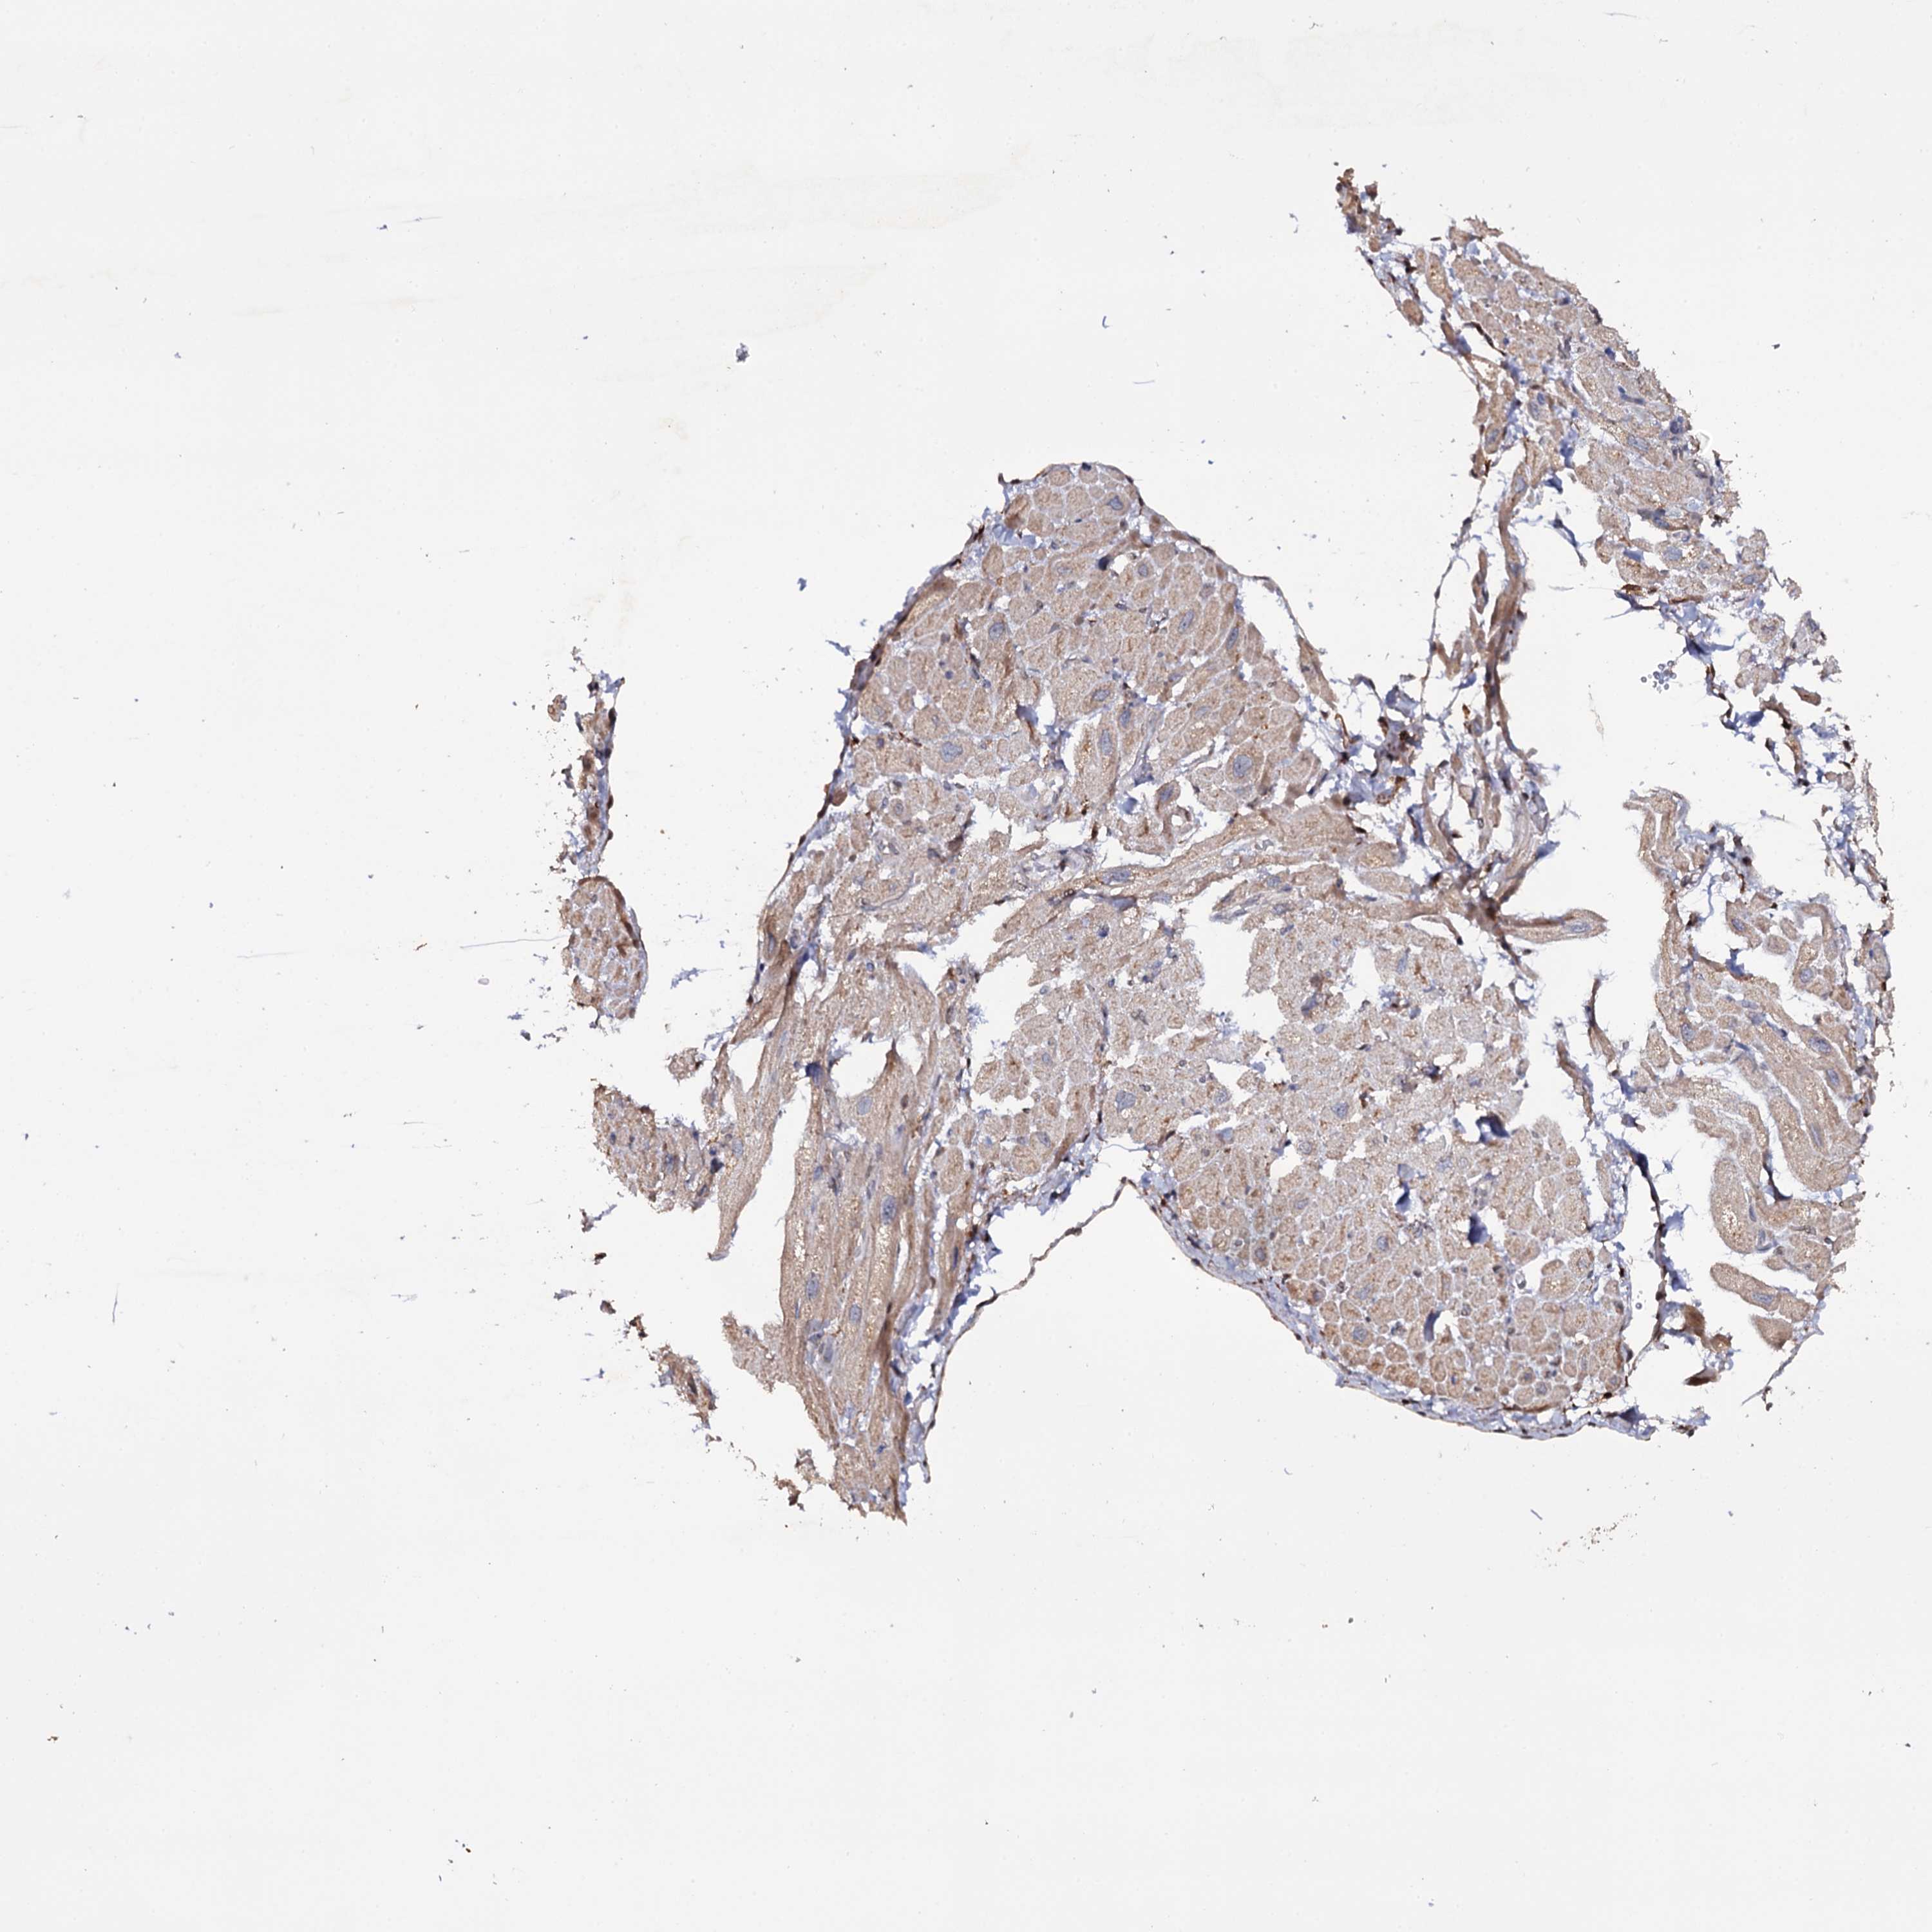

HEART MUSCLE - Antibody stainingi

Antibody staining in the annotated cell types in the current human tissue is reported as not detected, low, medium, or high, based on conventional immunohistochemistry profiling in selected tissues. This score is based on the combination of the staining intensity and fraction of stained cells.

Each image is clickable and will lead to virtual microscopy that enables deeper exploration of all samples and also displays staining intensity scores, fraction scores and subcellular localization as well as patient and tissue information for each sample.

Antibody HPA040403Antibody HPA058848

Cardiomyocytes LowNot detected